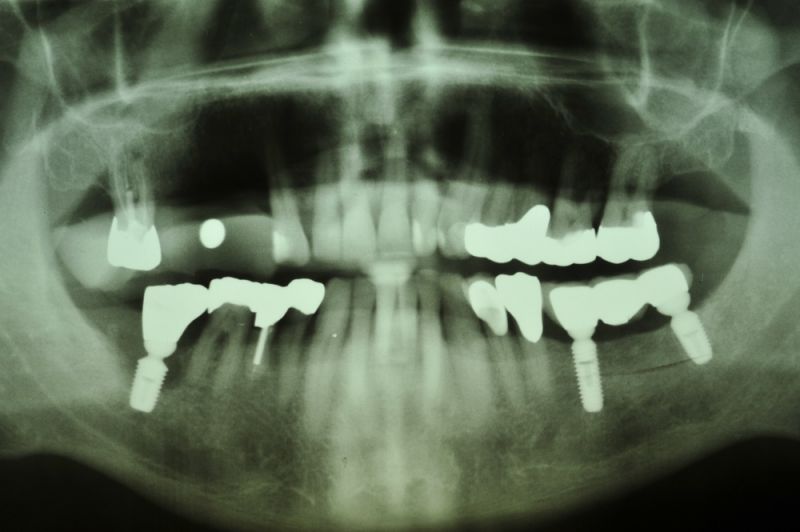

Vor ca. 20 Jahren wurde der Patient umfassend funktionstherapeutisch versorgt. Bereits zum damaligen Zeitpunkt waren die Zähne des Patienten vorgeschädigt und es lag eine Parodontalerkrankung vor.

In der Zwischenzeit sind vorgeschädigte Zähne verloren gegangen und wurden zum Teil durch Implantate ersetzt.